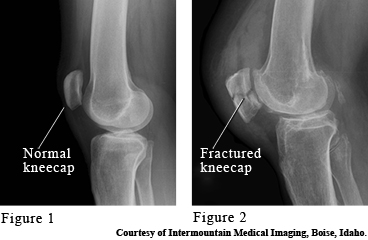

Images of a normal and broken kneecaps

The kneecap (patella) is a bone that protects the front of the knee joint. It takes the brunt of any blows to the knee, such as a fall onto the knee or hitting the knee against the dashboard. Symptoms of a broken kneecap (fracture) are swelling and pain, especially when moving the knee back and forth.